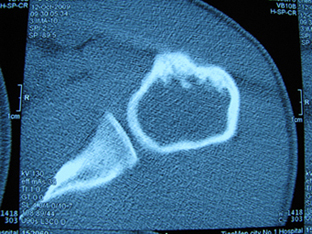

标题: X6404B:肱骨骨质破坏(CT片) [打印本页]

标题: X6404B:肱骨骨质破坏(CT片)

男,50岁,左肩部轻微疼痛,活动不便5个月就诊,近十天加重,无红肿热,间断理疗治疗无好转,既往5个月前左肩轻微拉伤史

骨巨?动脉瘤样骨囊肿?

内生软骨瘤。

内生软骨瘤。

内生软骨瘤?-----------

年纪大了,先要排除转移瘤。

髓腔内软组织肿块并斑片状钙化,考虑高分化软骨肉瘤可能性大。

考虑骨巨或动脉瘤样骨囊肿。

内生软骨瘤可能性大,期待结果。

孤立性骨囊肿。

内生软骨瘤可能性大

其内可见钙化,考虑软骨源性肿瘤,内生软骨瘤可能

但由于年龄较大,恶性软骨肉瘤待排

肱骨头内巨大软组织肿块并斑片状钙化,内生软骨瘤?骨巨细胞瘤?软骨粘液样纤维瘤?期待结果!

髓腔内软组织肿块并斑片状钙化,考虑高分化软骨肉瘤可能性大。

内生软骨瘤可能性大

肱骨头内巨大软组织肿块并斑片状钙化,内生软骨瘤?骨巨细胞瘤?软骨粘液样纤维瘤?期待结果

考虑内生软骨瘤?骨巨细胞瘤?

内生软骨瘤?骨巨细胞瘤?

先要排除转移瘤。